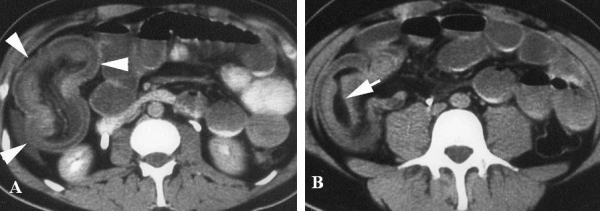

Hình 27: viêm túi thừa Meckel. A, Hình CT tiêm và uống thuốc cản quang ở bệnh nhân nam 22 tuổi, thấy cấu trúc hình ống, thành bắt cản quang, lòng chứa đầy dịch nằm dưới rốn ( mũi tên). Dày thành ruột non kế cận và thay đổi do viêm của mỡ mạc treo. B, CT cản quang tĩnh mạch ở bệnh nhân 49 tuổi, thấy cấu trúc tròn chứa dịch, bắt quang thành, có sỏi vôi bên trong (mũi tên). Thâm nhiễm mỡ kế cận. C, CT cản quang tĩnh mạch ở bệnh nhân 57 tuổi thấy đoạn ruột tận, tròn (đâu mũi tên)dính với đoạn xa hồi tràng (mũi tên). D. Bệnh nhân 76 tuổi. Thấy có đoạn ruột tận, bắt nguồn từ đoạn xa manh tràng bên trong chứa đầy dịch (mũi tên),thâm nhiễm mỡ xung quanh (dấu hoa thị). Tất cả sau mổ là viêm túi thừa Meckel. (Hình A, B, C: Angela D. Levy, Christine M. Hobbs (2004). Meckel Diverticulum: Radiologic Features with Pathologic Correlation. RadioGraphics 24:584. Hình D: Alexandra Platon , Pascal Gervaz (2010). Computed tomography of complicated Meckel’s diverticulum in adults. Insights Imaging 1:56).